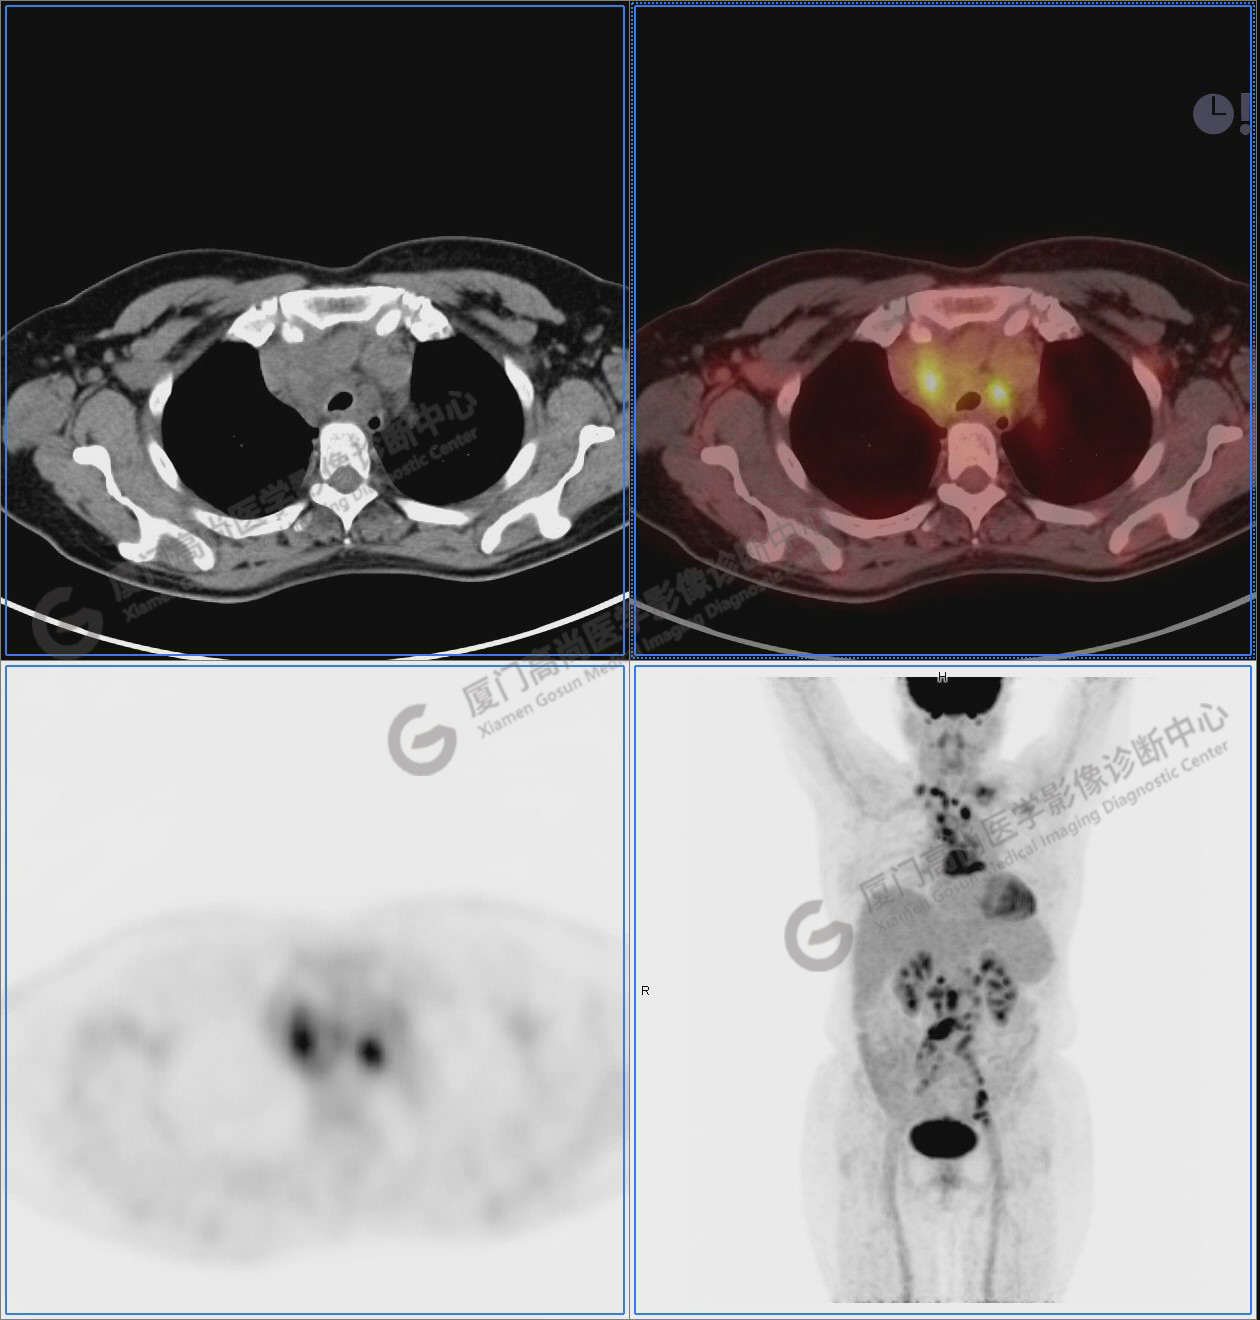

圖1:PET/CT全身圖像

圖2-9:雙側(cè)鎖骨區(qū)、縱隔、右側(cè)內(nèi)乳區(qū)、腸系膜緣、腹膜后、雙側(cè)髂血管旁及盆腔多發(fā)腫大淋巴結(jié)影,代謝不同程度增高,考慮為轉(zhuǎn)移。

圖4